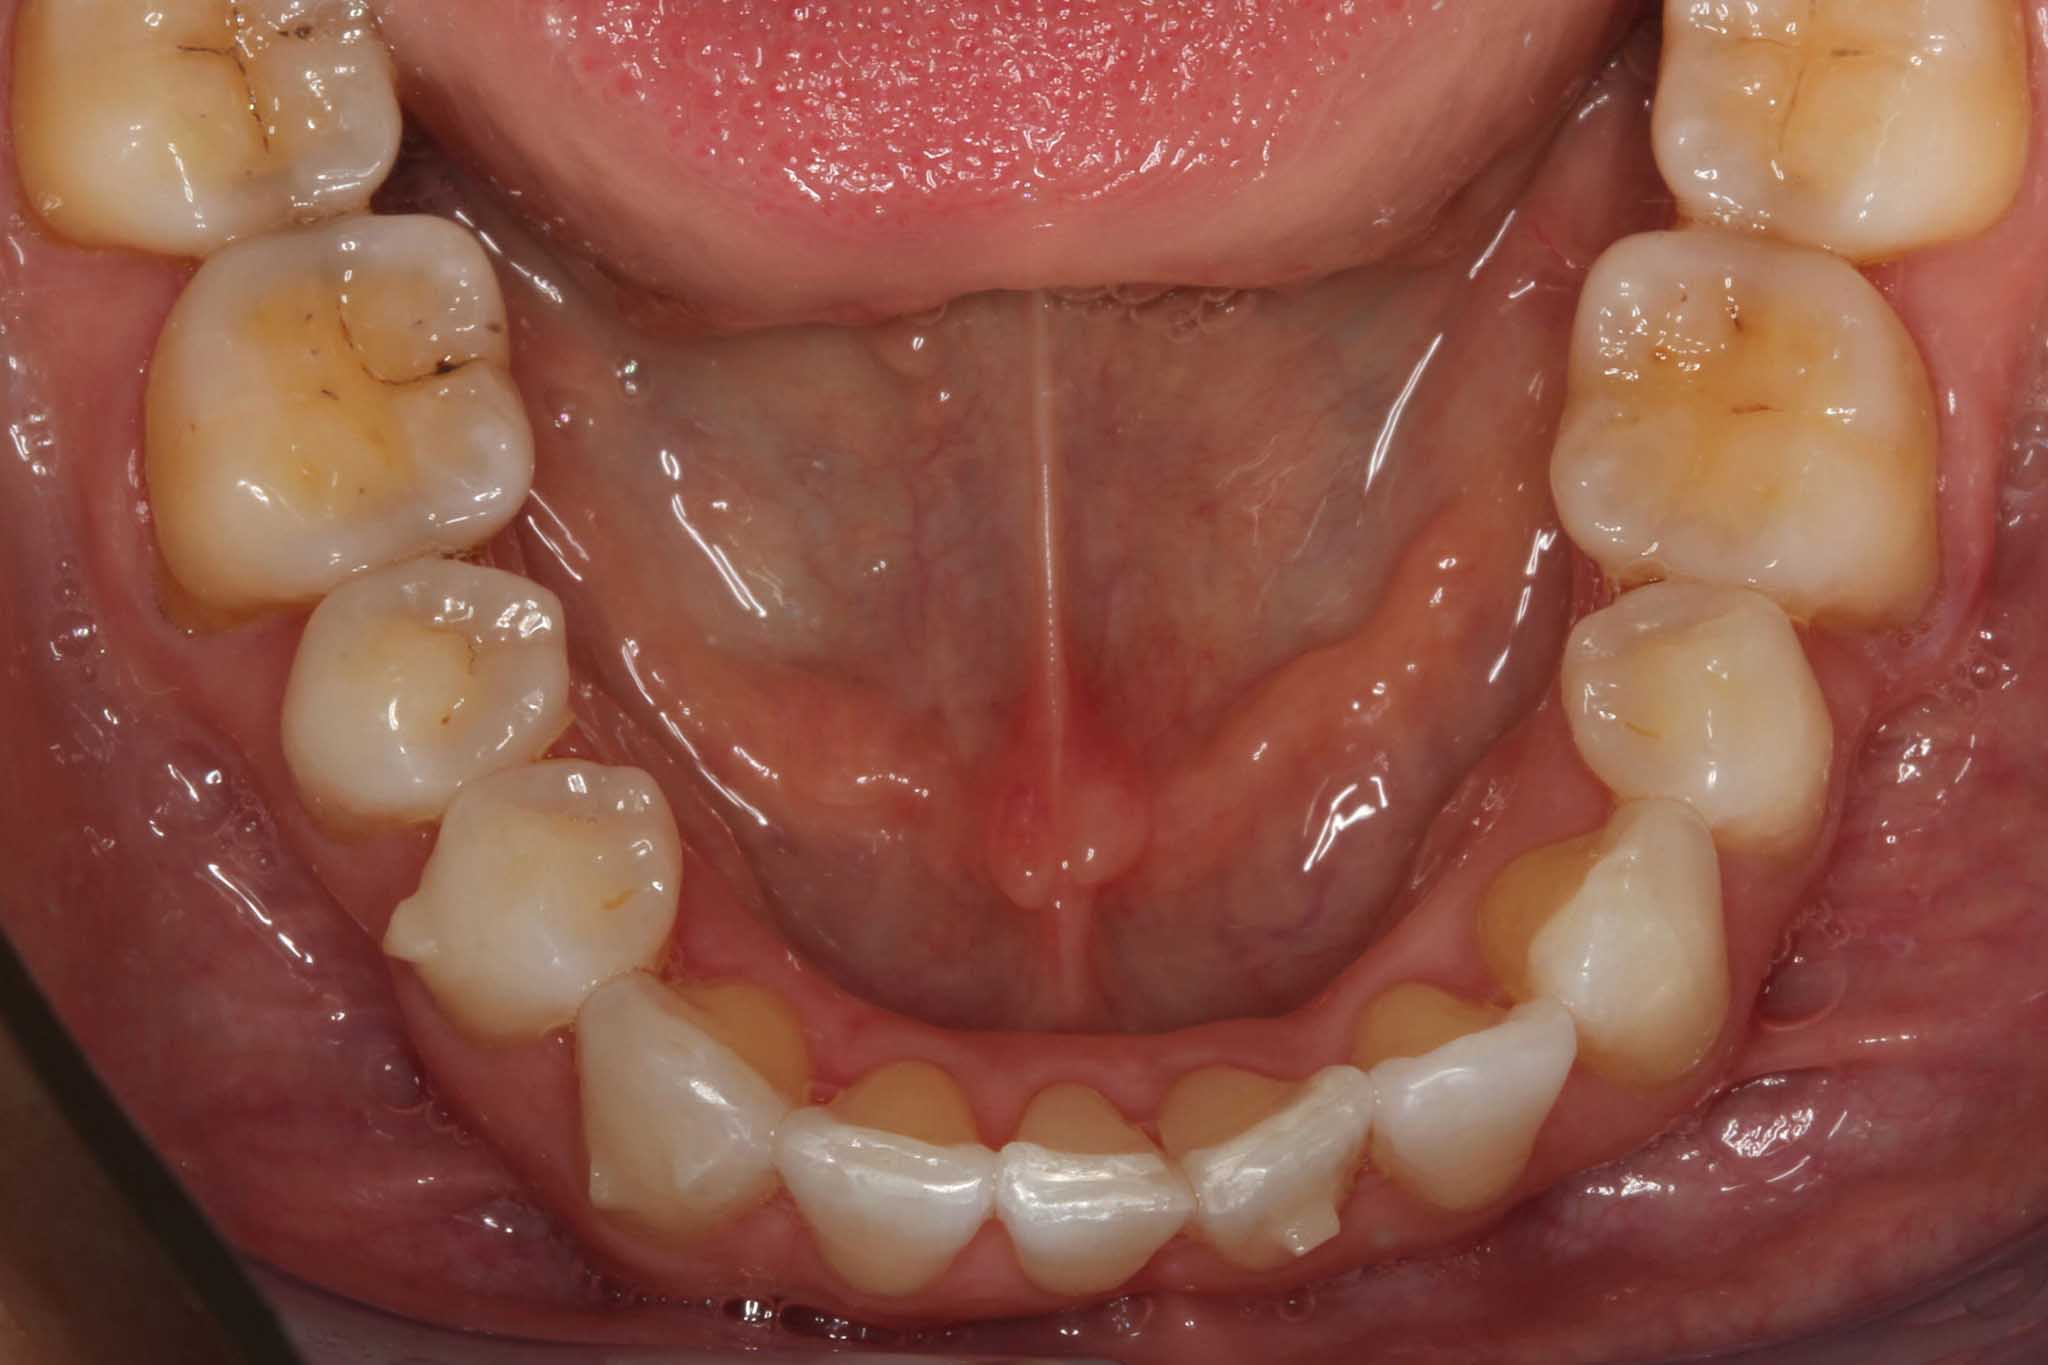

Før- og etterbilder – Resultater fra retainerbehandling

Bildet viser retainertråd festet bakpå underkjevens fortenner.